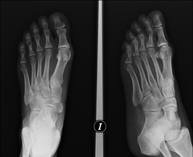

- RX Extremitats

Tècnica que usa els raigs X a través de la qual s'obtenen imatges de l'interior de les extremitats per al seu estudi, especialment dels ossos. Indicacions: traumatisme, infeccions articulars. - RX Artrografia

Estudi que mitjançant una radiografia de la mà permet valorar, en funció del desenvolupament dels ossos, l'edat del pacient i determinar si existeix un retard o un creixement superior pel que correspon a la seva edat. - RX Malucs pediatria

Tècnica que usa els raigs X a través de la qual s'obtenen imatges del càvum per al seu estudi. Indicacions: dificultat respiratòria, regurgitació, otitis de repetició. - RX Edat òssia

Estudi que mitjançant una radiografia de la mà permet valorar, en funció del desenvolupament dels ossos, l'edat del pacient i determinar si existeix un retard o un creixement superior pel que correspon a la seva edat. - RX Sins paranasals

Tècnica que usa els raigs X a través de la qual s'obtenen imatges de la totalitat d'ambdues extremitats inferiors per al seu estudi, amb la valoració especialment de la presència de dismetries entre elles. - RX Extremitats

Tècnica que usa els raigs X a través de la qual s'obtenen imatges d'ambdues extremitats per al seu estudi. - RX Malucs